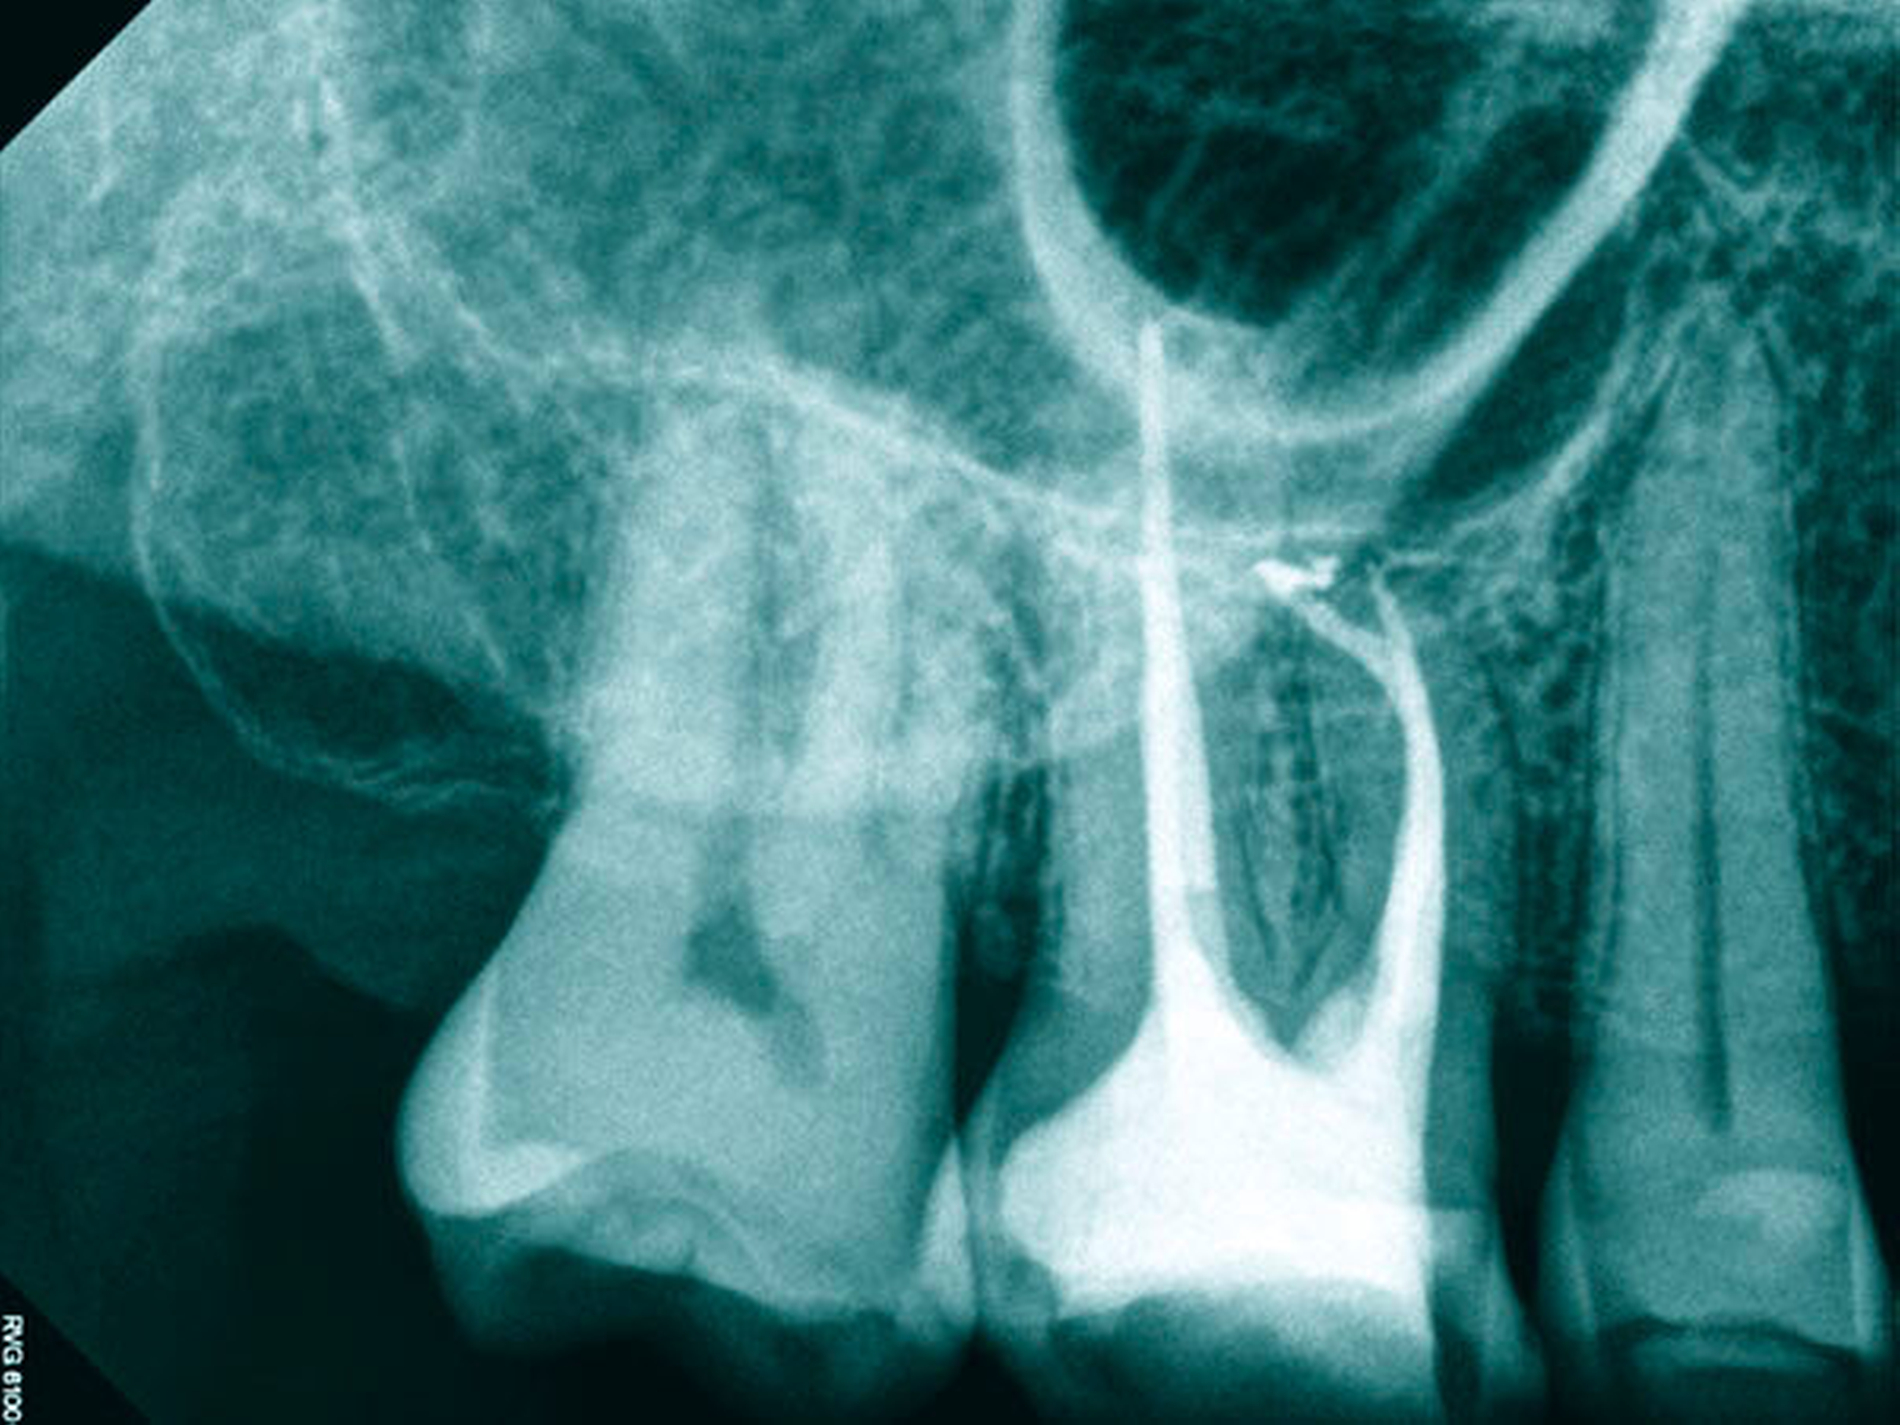

Die aktuelle Forschung kann auf hochauflösende Verfahren zur Ermittlung von Wurzelkanalsystemen zurückgreifen. Die destruktiven Verfahren werden dabei mehr und mehr von nondestruktiven Verfahren (MikroCT, NanoCT, MRT) abgelöst [Parkinson & Sasov, 2008; Paqué et al., 2010] (Abbildungen 2 und 3). Mit der dentalen Digitalen Volumentomografie (DVT) gelingt es erstmals am Patienten, die tatsächliche Form und den Verlauf von Wurzeln in Beziehung zu pathologischen Prozessen darzustellen (Abbildung 4) und aus der Form der Wurzel Rückschlüsse auf die Anzahl und die genaue Lage der Wurzelkanäle zu ziehen [DVT-Leitlinie DGZMK S2, 2009; Patel, 2009; Michetti et al., 2010].

Schließlich werden mit der mechanischen Erweiterung und konischen Ausformung der Wurzelkanäle die Voraussetzungen für einen dichten Verschluss des Wurzelkanalsystems geschaffen, damit eine Rekolonisierung von endodontischen Hohlräumen vermieden werden kann (Abbildung 7) [Klimm, 2003; Hülsmann & Schäfer, 2005]. Im Ergebnis einer vollständigen antimikrobiellen Therapie bilden sich ausgedehnte periapikale Aufhellungen und pathologische Prozesse der Kieferhöhle vollständig zurück und erfordern keinen weiteren chirurgischen Eingriff (Abbildung 8).